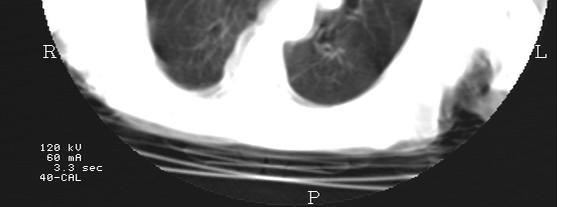

扫描时机子并没报错误代码,而是扫描的图像发现了改变。请看图。

这里2张图是同一个病人的,后面一张最下面3条横线(那是扫描床)平行的,正常图像。前面一张最下面我们可以看见完全不清晰了,而且还可以看见左右歪曲,异常图像。

另外,我用不同的扫描时间和不同的mA值分别进行扫描,其中3.3s 40mA 以及5s  40、60、80、100mA扫描的图像都是正常的,但是用3.3s 60、80、100mA扫描就出现不正常的图像了。请大家看图。